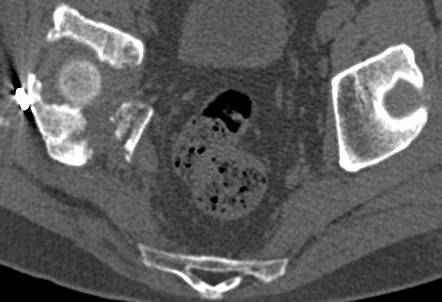

высылаю дополнительно сканы.

Судя по представленным реконструкциям (не очень хорошего качества - много наводок)

мы имеем дело с полупоперечным переломом у которого отломался задний край или его отломали, превратив перелом в полный двухколонный.

По отдельным срезам и тем более по реконструкции трудно судить о сращении крыла и задней колонны с осевым скелетом.

Все выступающие коллеги высказались насчет необходимости стандартных снимков по Judet, потому что для определения тактики лечения переломов вертлужной впадины 3Д снимки малоинформативны.

Из того минимума, что представлено, мне кажется, мы имеем дело с двухколонным переломом вертлужной впадины. Обычно медиальный (центральный) "вывих" головки встречаются в сложных двухколонных переломах со смещением.

Дополнительные сканы